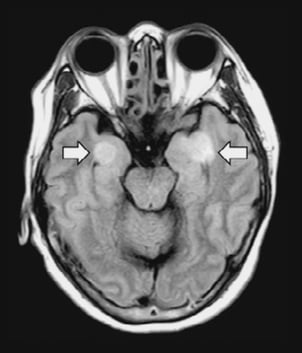

Un autre ensemble frappant de symptômes chez les patients COVID-19 se concentre sur le cerveau et le système nerveux central.

Les neurologues évaluent à 5% à 10% le nombre de leurs patients atteints de coronavirus dans leurs services. Mais ils pensent qu'il s'agit probablement "d'une sous-estimation flagrante" du nombre de patients dont le cerveau est en difficulté, en particulier parce que beaucoup sont sous sédation et sous ventilateurs.

Encéphalite, convulsions, pertes brèves de connaissance, perte d'odorat... témoignent que le cerveau n'est pas épargné.

- Les récepteurs ACE2 sont présents dans le cortex neural et le tronc cérébral, mais on ne sait pas comment le virus pourrait pénétrer dans le cerveau et interagir avec ces récepteurs.